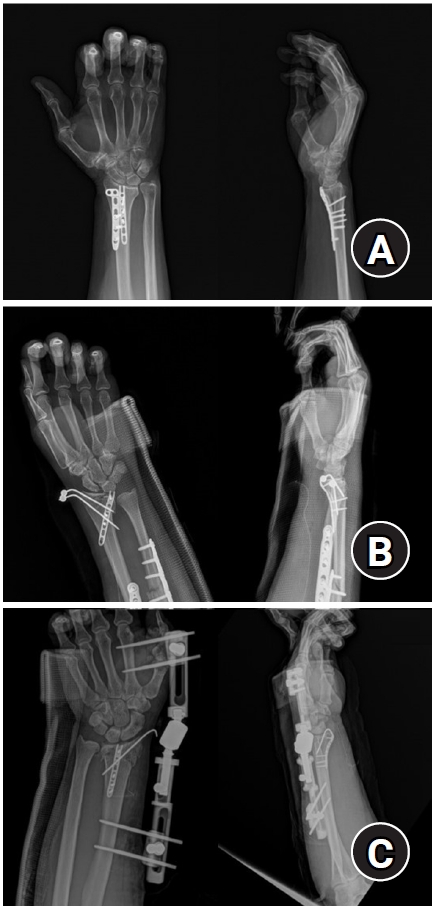

Setting

Fig. 3.

Postoperative radiographs (anteroposterior and lateral). (A) Volar articular marginal fragment of the distal radius fixed by two plates: a standard 2.4 mm LCP-L distal radius plate (Synthes) and a 2.0 mm locking compression plate distal ulnar hook plate (Synthes). (B) Additional percutaneous pinning after plating. (C) Additional percutaneous pinning and external fixator after plating.

jmt-2025-00241f3.jpg

Fig. 1. Surgical procedure. (A) Volar lunate facet fragment after distal radius fracture. (B) Reduction of the fragment and temporary fixation with a Kirschner wire. (C) Application of a hook plate to the volar aspect of the distal radius; additional percutaneous pinning was performed when plate fixation alone was insufficient.

Fig. 3. Postoperative radiographs (anteroposterior and lateral). (A) Volar articular marginal fragment of the distal radius fixed by two plates: a standard 2.4 mm LCP-L distal radius plate (Synthes) and a 2.0 mm locking compression plate distal ulnar hook plate (Synthes). (B) Additional percutaneous pinning after plating. (C) Additional percutaneous pinning and external fixator after plating.